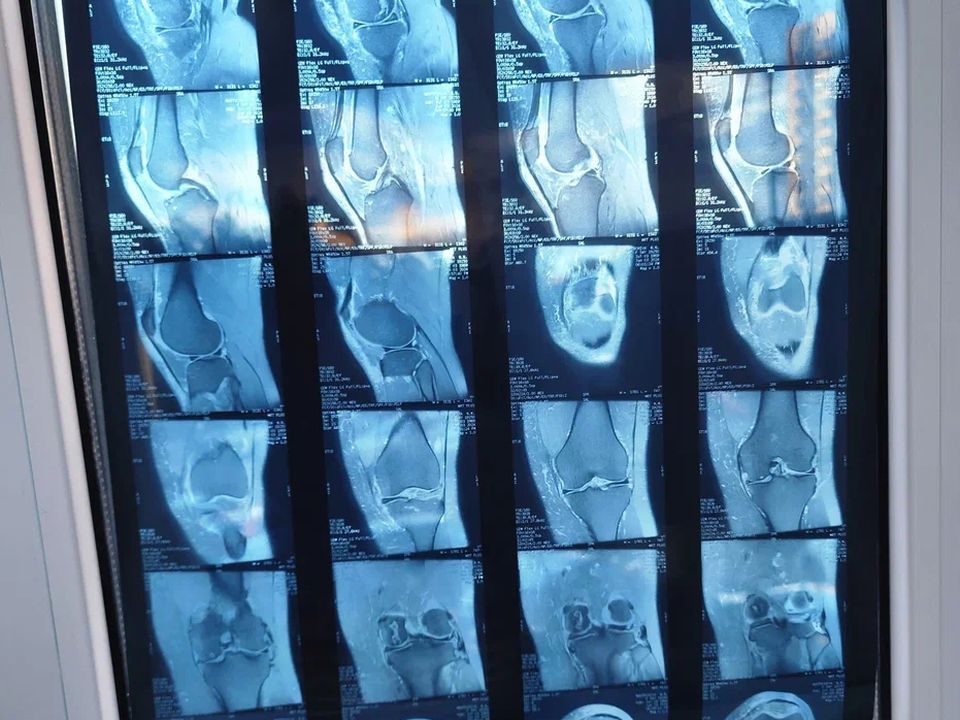

- При артрозе: главный метод — рентген или МРТ. На снимках будет четко видно сужение суставной щели и изменения в хряще.